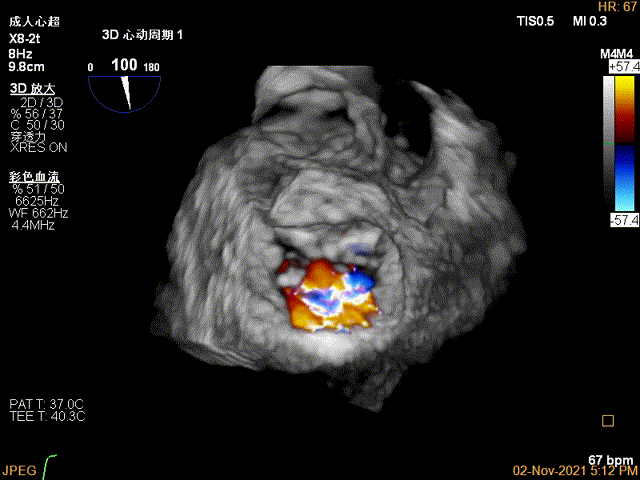

3D证实夹子AC区残余脱垂被禁锢住

3D-color证实无明确残余分流